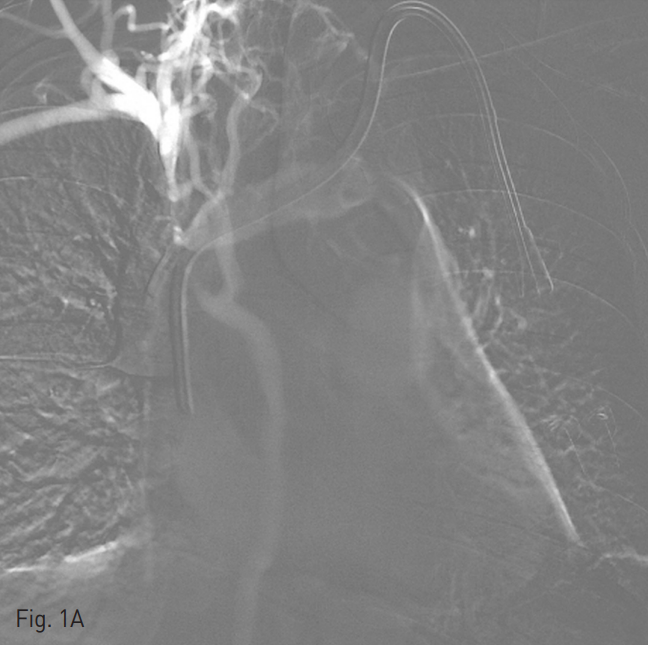

양측 내경정맥을 통한 정맥 조영술에서 상대정맥이 완전히 폐색되어 있으며 (Fig. 1A-B) 이를 대체하기 위해 우측 대퇴정맥에 투석용 카테터를 삽입하였지만 이 또한 10일 후 카테터 주변으로 혈전이 발생하였다(Fig 1C). 이어서 허리 경유 접근을 통해 투석용 카테터 삽입을 위해 하대정맥 천자를 시도하였으며 6 Fr sheath까지 들어간 후에 천자된 곳이 대동맥임을 알게 되어 대동맥에 stent-graft를 넣었다 (Fig. 2A). 투석이 급하여 일단 간정맥을 통하여 투석용 카테터를 삽입하였으나 (Fig. 1D) 이 역시 혈전으로 인한 기능 부전으로 수 차례 교환술을 시행하였다.

Fig. 1. Diffuse venous thrombosis of both internal jugular and femoral veins.

A-B. Venograms via right (A) and left (B) in ternal jugular veins show complete obstruction of superior vena cava with development of collateral flow (A and B).